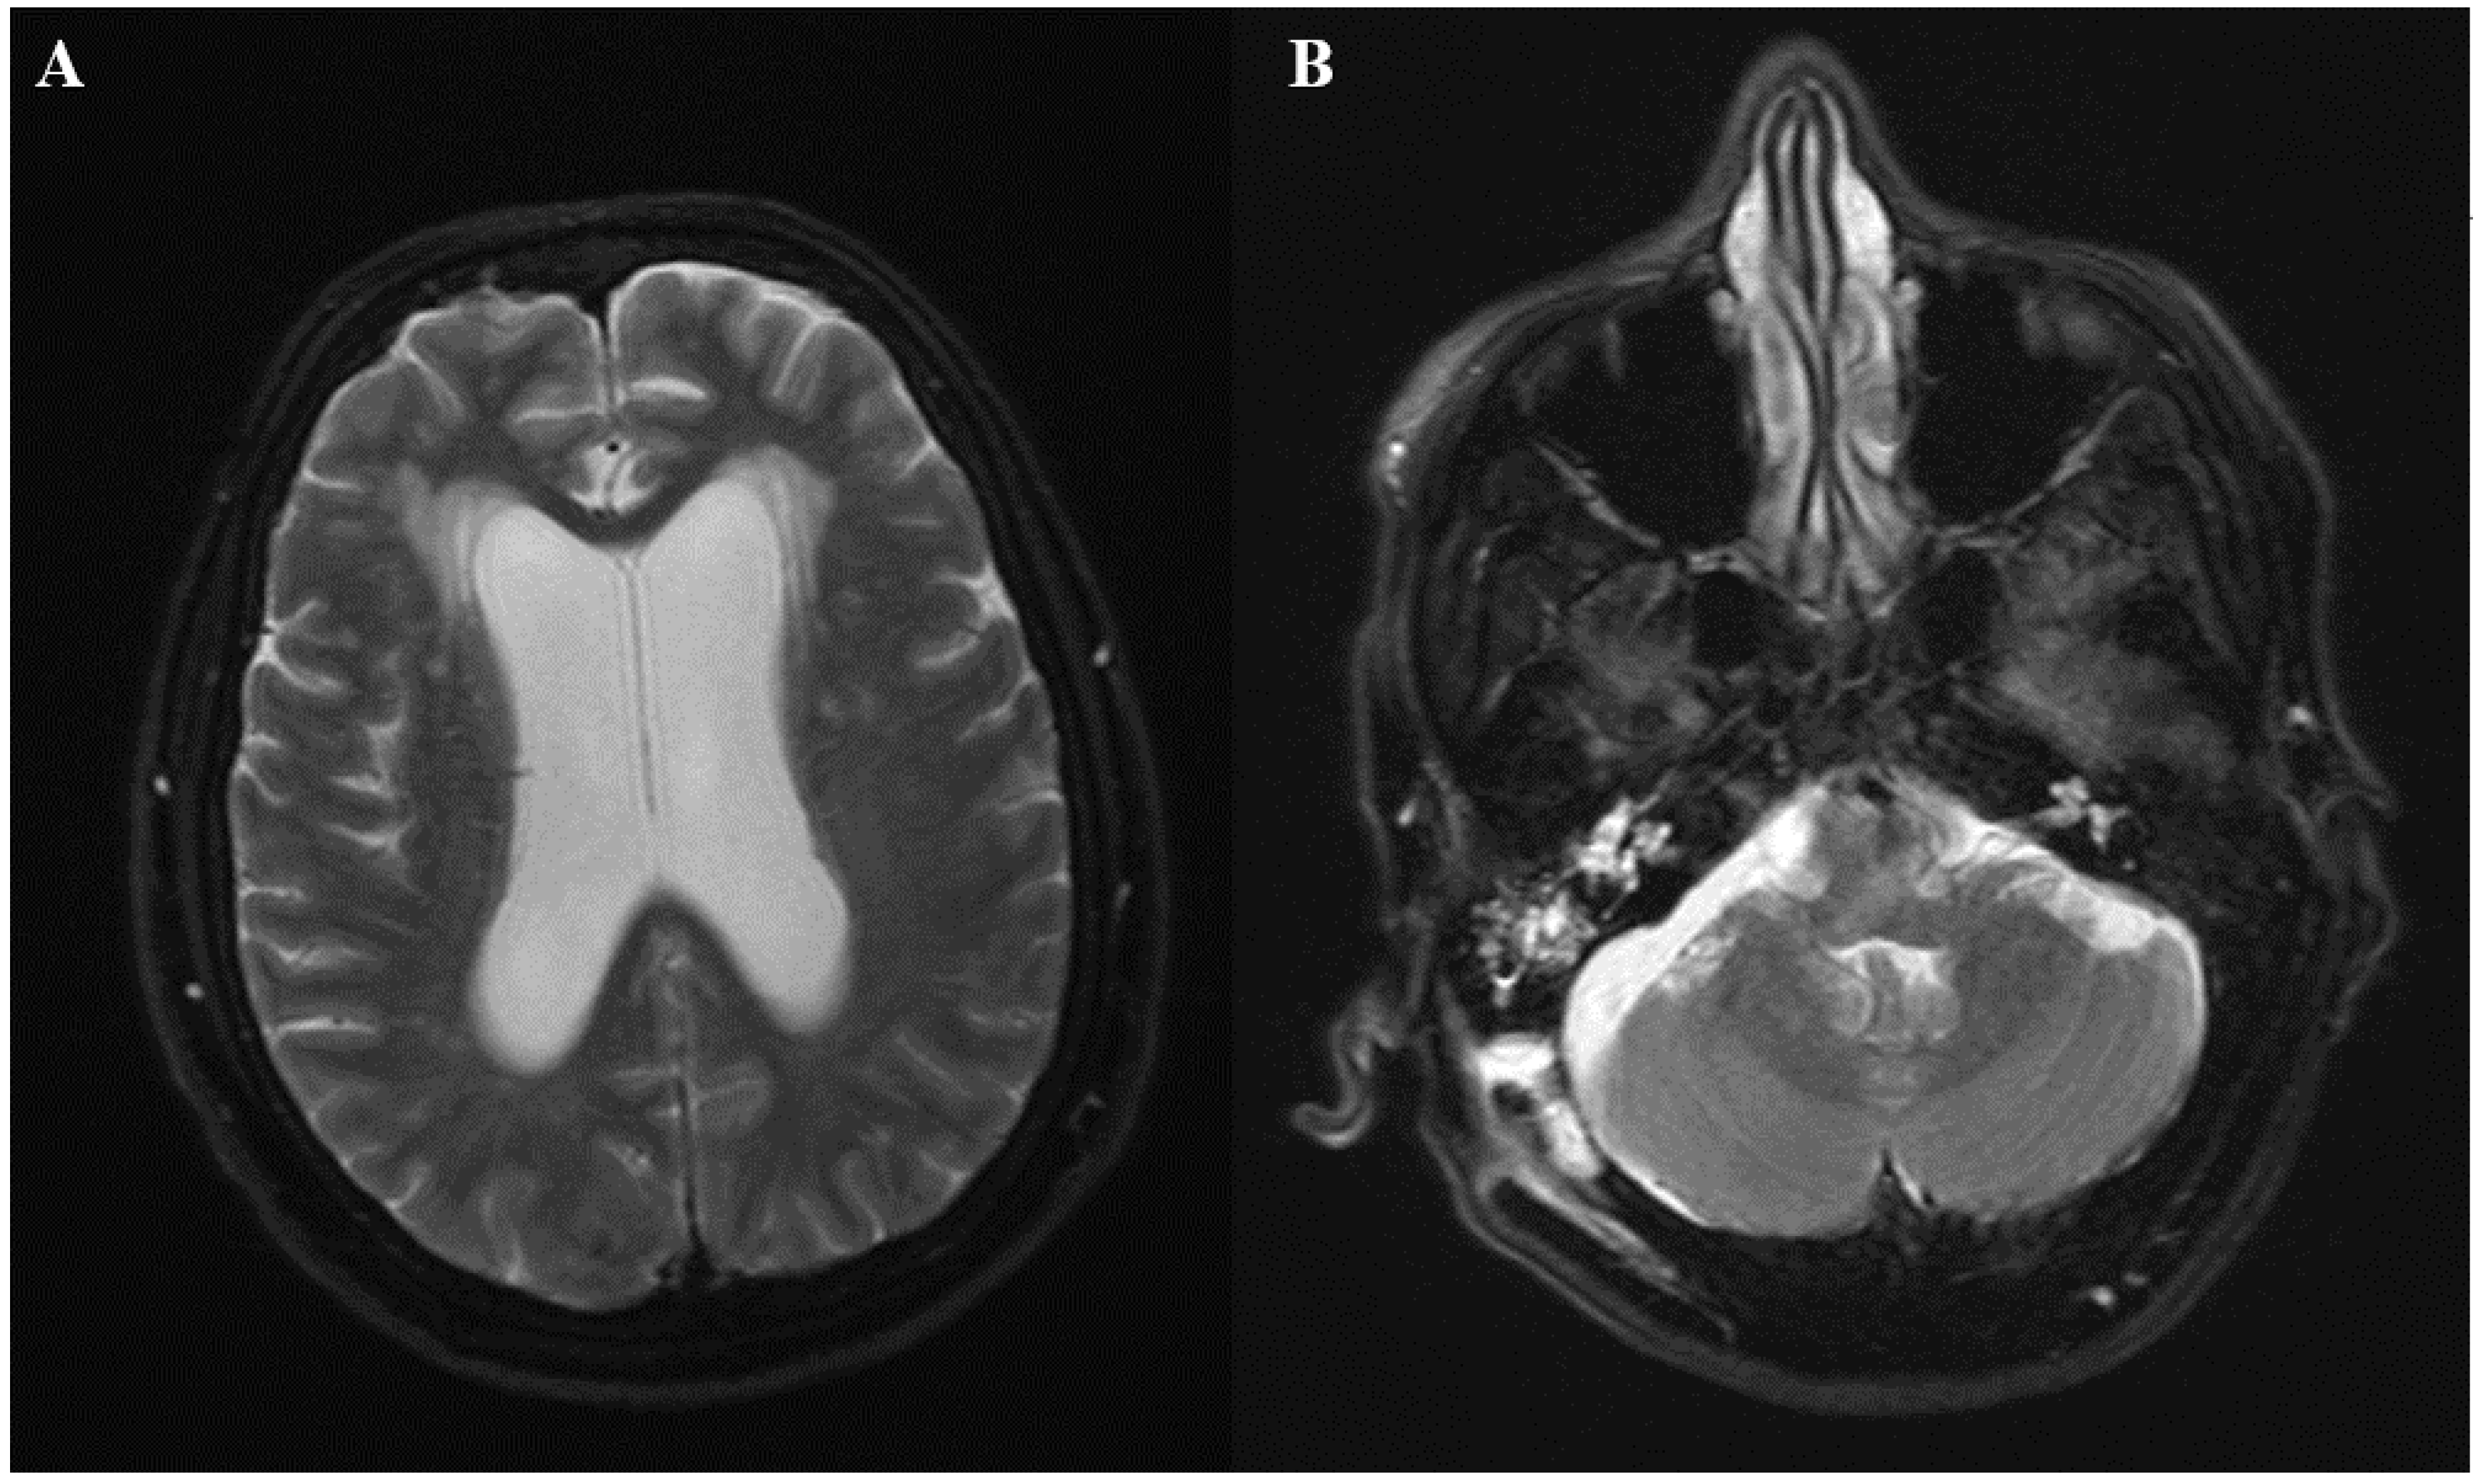

Figure 1.

(A) Axial T2-weighted MRI (magnetic resonance imaging)showing diffuse leptomeningeal enhancement and moderately dilated ventricles (B) T2-weighted MRI showing a right cerebellar extra-axial collection of approximately 1 cm in diameter.